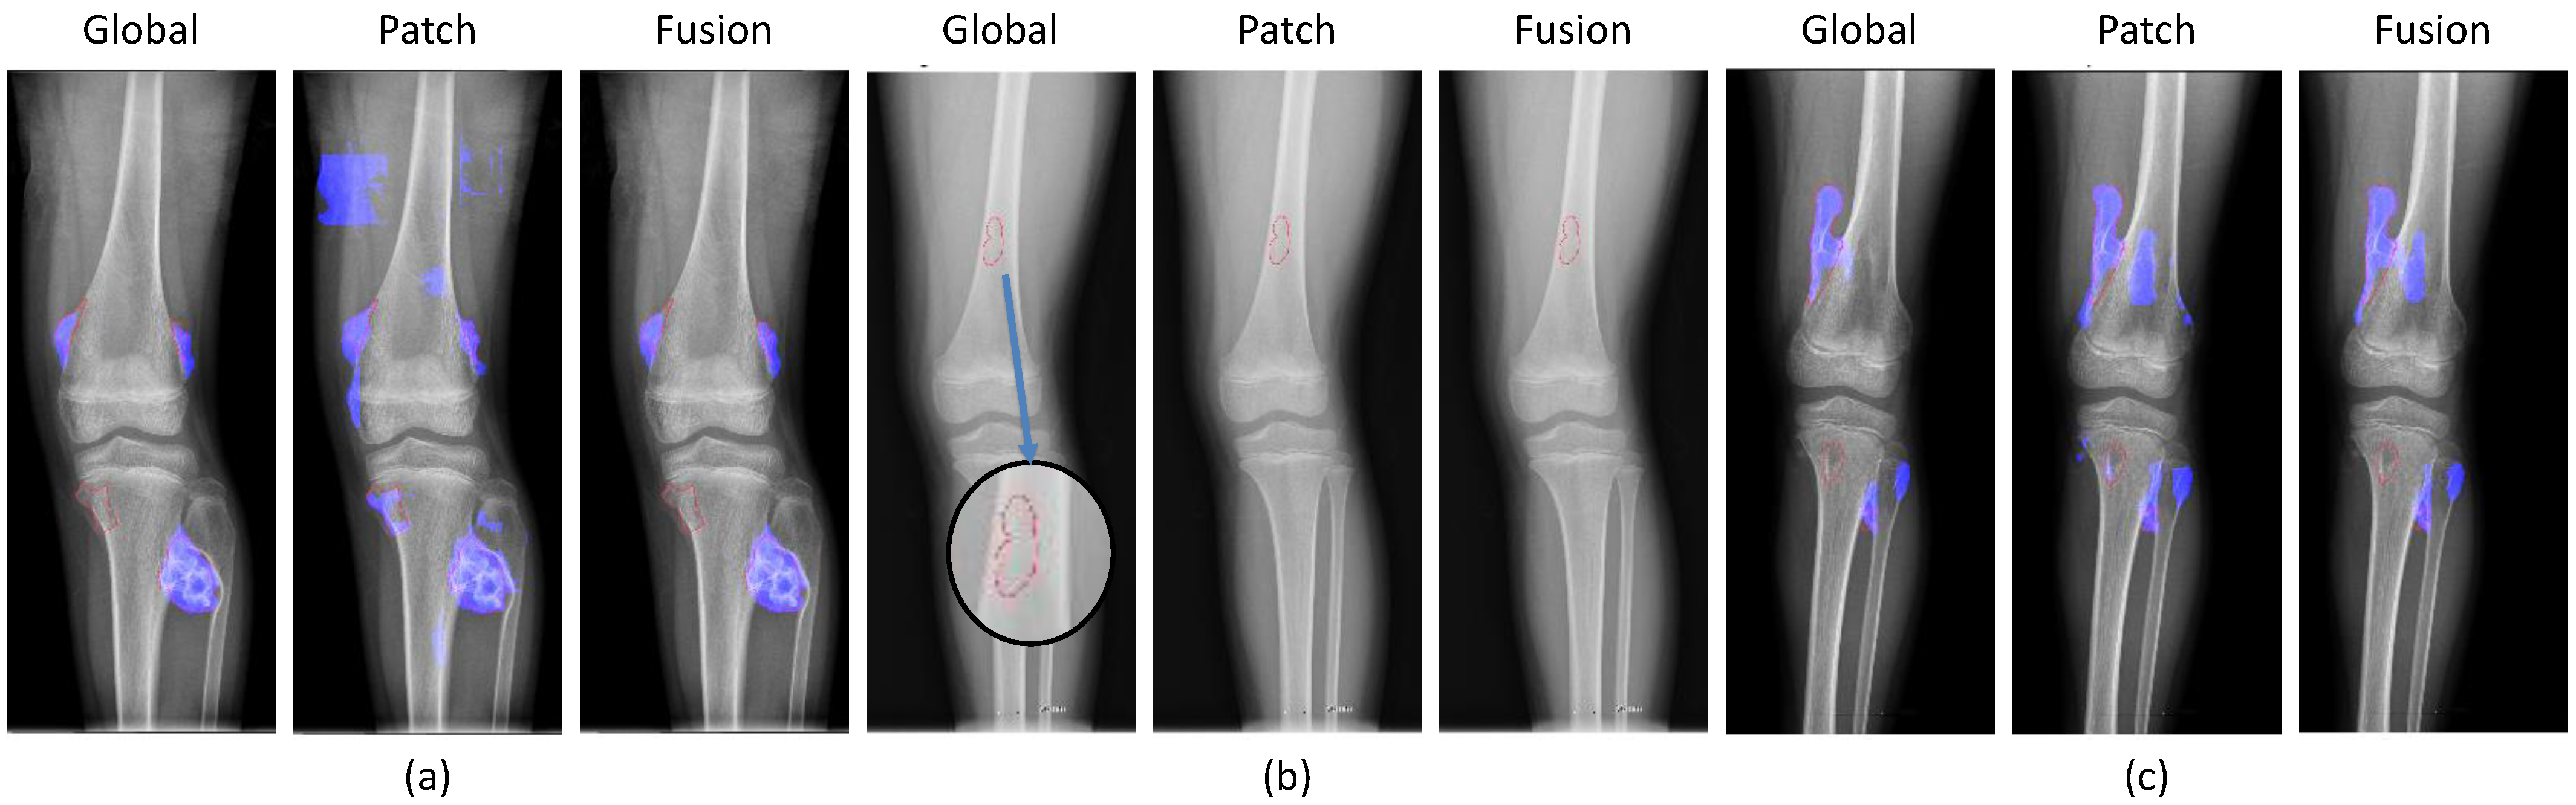

2.1. CNUH Dataset and Challenges